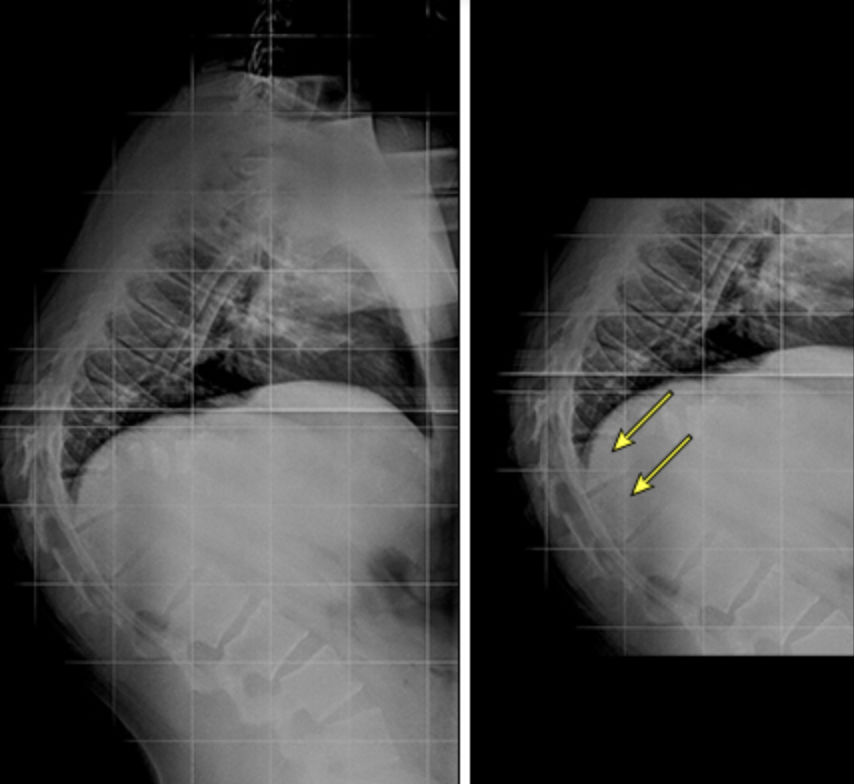

真性驼背的侧位 X 光片

可见患儿脊柱后凸角度非常锐利

图片来源:uptodate